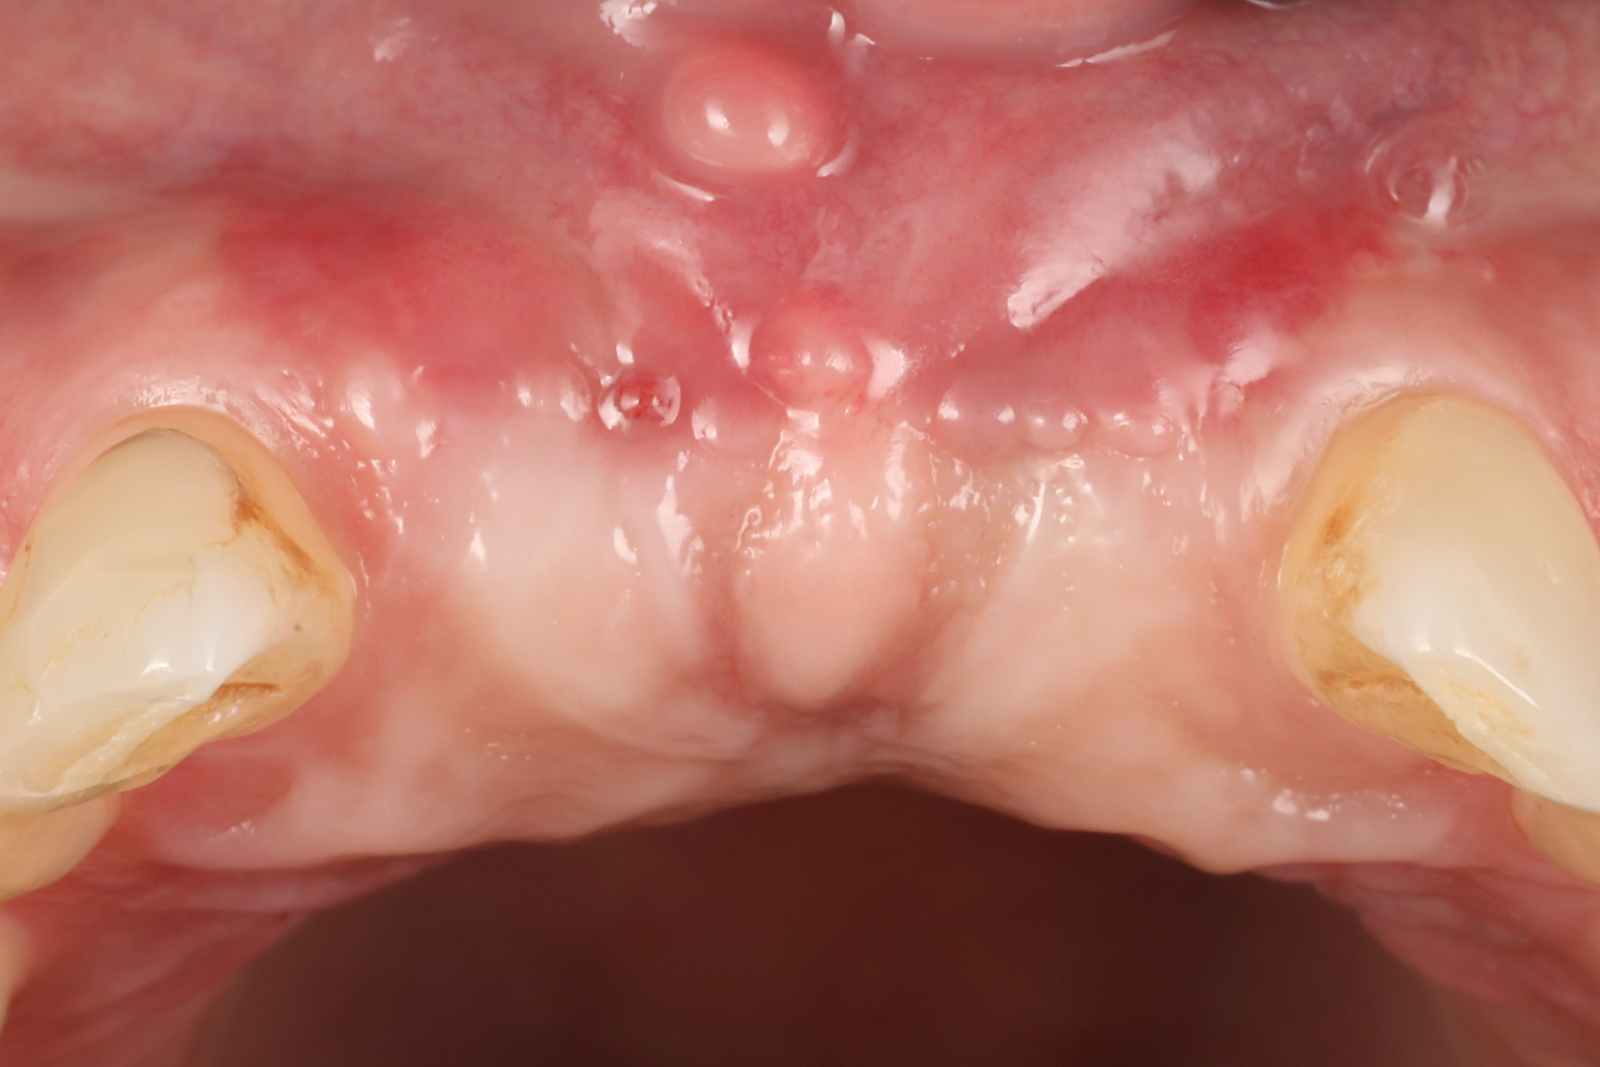

A 46-year-old systemically and periodontally healthy woman presented to the Graduate Periodontics Clinic at the University of Michigan School of Dentistry with the chief complaint of poor esthetics of her smile due to two dental implants (Nos. 8 and 9) showing their metal components (Figure 1). The patient reported that the implants had been placed 15 to 20 years previously after an accident. Clinical examination revealed that the implants had probing depths within 3 mm (facial probing depth of 3-2-3 mm for implant No. 8 and 2-2-2 mm for implant No. 9), no bleeding on probing, and no suppuration; the implants were therefore diagnosed as healthy (Figure 1 and Figure 2). The papilla between the two implants was deficient on the buccal aspect. The implants were buccally positioned, and a substantial lack of soft-tissue volume was noted.

Fig 1. Clinical view at presentation.

Figure 1